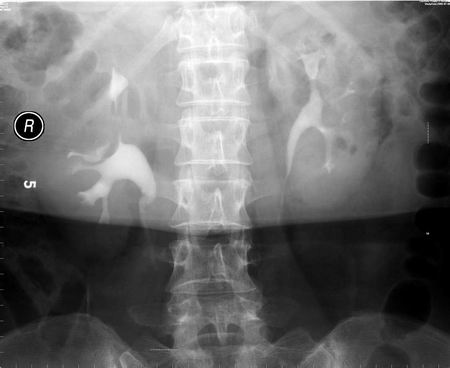

以下是引用向医生在2005-2-3 16:50:59的发言:[br]右侧肾盂上部及上肾盏受压,压迹呈弧形,边缘光滑,肾盏无侵蚀现象,局部肾轮廓似有增大。[br]意见:右肾上极占位。

以下是引用lkc8963在2005-2-9 20:43:32的发言:[br]支持右上极良性占位性病变.右肾区无钙化,局部无明显突出,肾盏受压变形,受压肾盏间似见片状造影剂充盈,功能正常,可能为囊肿或肾盏憩室,因为病变与收集系统相通.